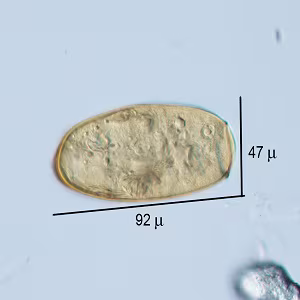

A 35-year-old female tourist who visited Vietnam presented with symptoms of headache, cough, fatigue and weight loss about ten weeks after returning from her trip. A stool specimen was collected in 10% formalin, concentrated by ethyl acetate method (FEA), and viewed under light microscopy for routine ova and parasite (O&P) examination. Figures A–C show what was observed in a wet mount of the FEA concentrate. The objects of interest measured 88-92 micrometers long by 47-48 micrometers wide.

Figure A